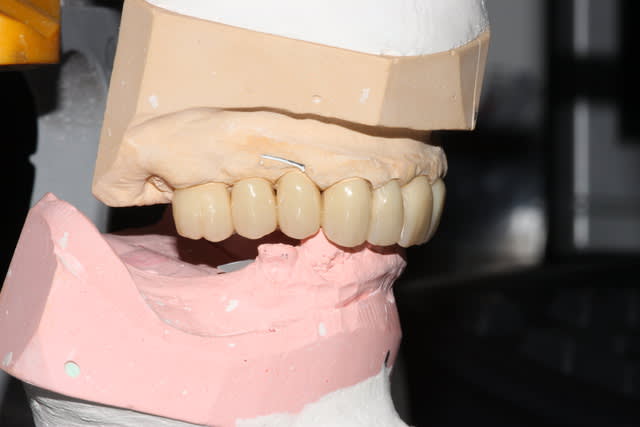

Suite du boulot: le bas

Quelques semaines plus tard, on prépare 37 36 34, ainsi que la 44, conservée vivante. J'ai hésité à aller chercher un ancrage radiculaire, étant donné le peu de hauteur de la couronne clinique, en fin de compte la CCM sera collée au superbond. Là encore, surfaçage/curetage rotatif des poches le jour de la préparation (sur 36 et 37 exclusivement)

Provisoires.

Séances suivantes (2 séances je crois), reprise des traitements endo, réalisation des RCR/tenons fibrés. Empreinte.

Réalisation des CCM+bridge selon courbe d'occlusion idéalisée, je retoucherai le provisoire maxillaire le jour de la pose.

Pose du bas, nous sommes en décembre, à la mandibule tout est propre, on va pouvoir s'occuper plus sérieusement du maxillaire à la rentrée.

(photos avec pro en place réalisées au fauteuil)

Du coup, pour finir:

-En janvier, c'est reparti: reprise de traitement 12 13 14. Comme je le disais, les RCR 15 16 sont en bon état, les endos asyptomatiques même si pas parfaites: je n'y ai pas touché, l'avenir me dira si j'ai eu raison.

Inlays-core 12 13 14, j'aurais pu réaliser des RCRs mais je ne me sentais pas de paralléliser les 9 piliers à l'oeil.

Le jour de l'empreinte des IC, on prend également une empreinte alginate du bridge pro en place.

Ainsi, par CFAO et en se basant sur les tissus mous périphériques, le labo nous a confectionné un duplicata du bridge pro en résine usinée, qui nous servira à enregistrer la RIM définitive: je n'aurai aucune retouche à y apporter.

Puis classique essayage d'armature (parfaite, merci le labo), et pose. Réglages occlusaux le lendemain.

Photos de l'occlusion avant les réglages occlusaux, tout juste sorti du labo. J'ai diminué les contacts sur la 23 en entrée de cycle, et sur la 21 en incision. (bleu en statique, rouge en cycles masticatoires)

Pose des implants prévue pour cet été, donc couronnes vers Noël probablement.

Je peaufinerai probablement encore un peu l'occlusion dans 6 mois, lorsqu'on posera 45 46.